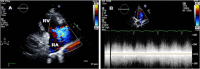

Case presentation: In this case report, we describe a 23-year-old patient with an acute onset of chest pain, shortness of breath, palpitations and dizziness starting 2 days prior to presentation to the emergency department. The patient was initially treated for presumed pulmonary embolism overnight while awaiting CTPA the next morning. However, further examination by the inpatient medical team demonstrated a continuous machinery cardiac murmur. Subsequent echocardiography demonstrated an acutely ruptured SVA with shunting to the right atrium. Emergency surgical repair resulted in an excellent outcome for the patient.